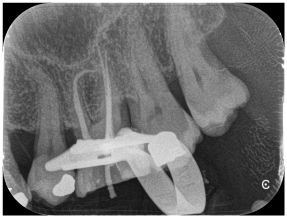

Figure 8. Preliminary endo-oral radiography of a maxillary second premolar.

Figure 9. Ni-Ti rotary instrument inserted into root canal up to working length.

Figure 10. Final endo-oral radiography, showing complete root filling.